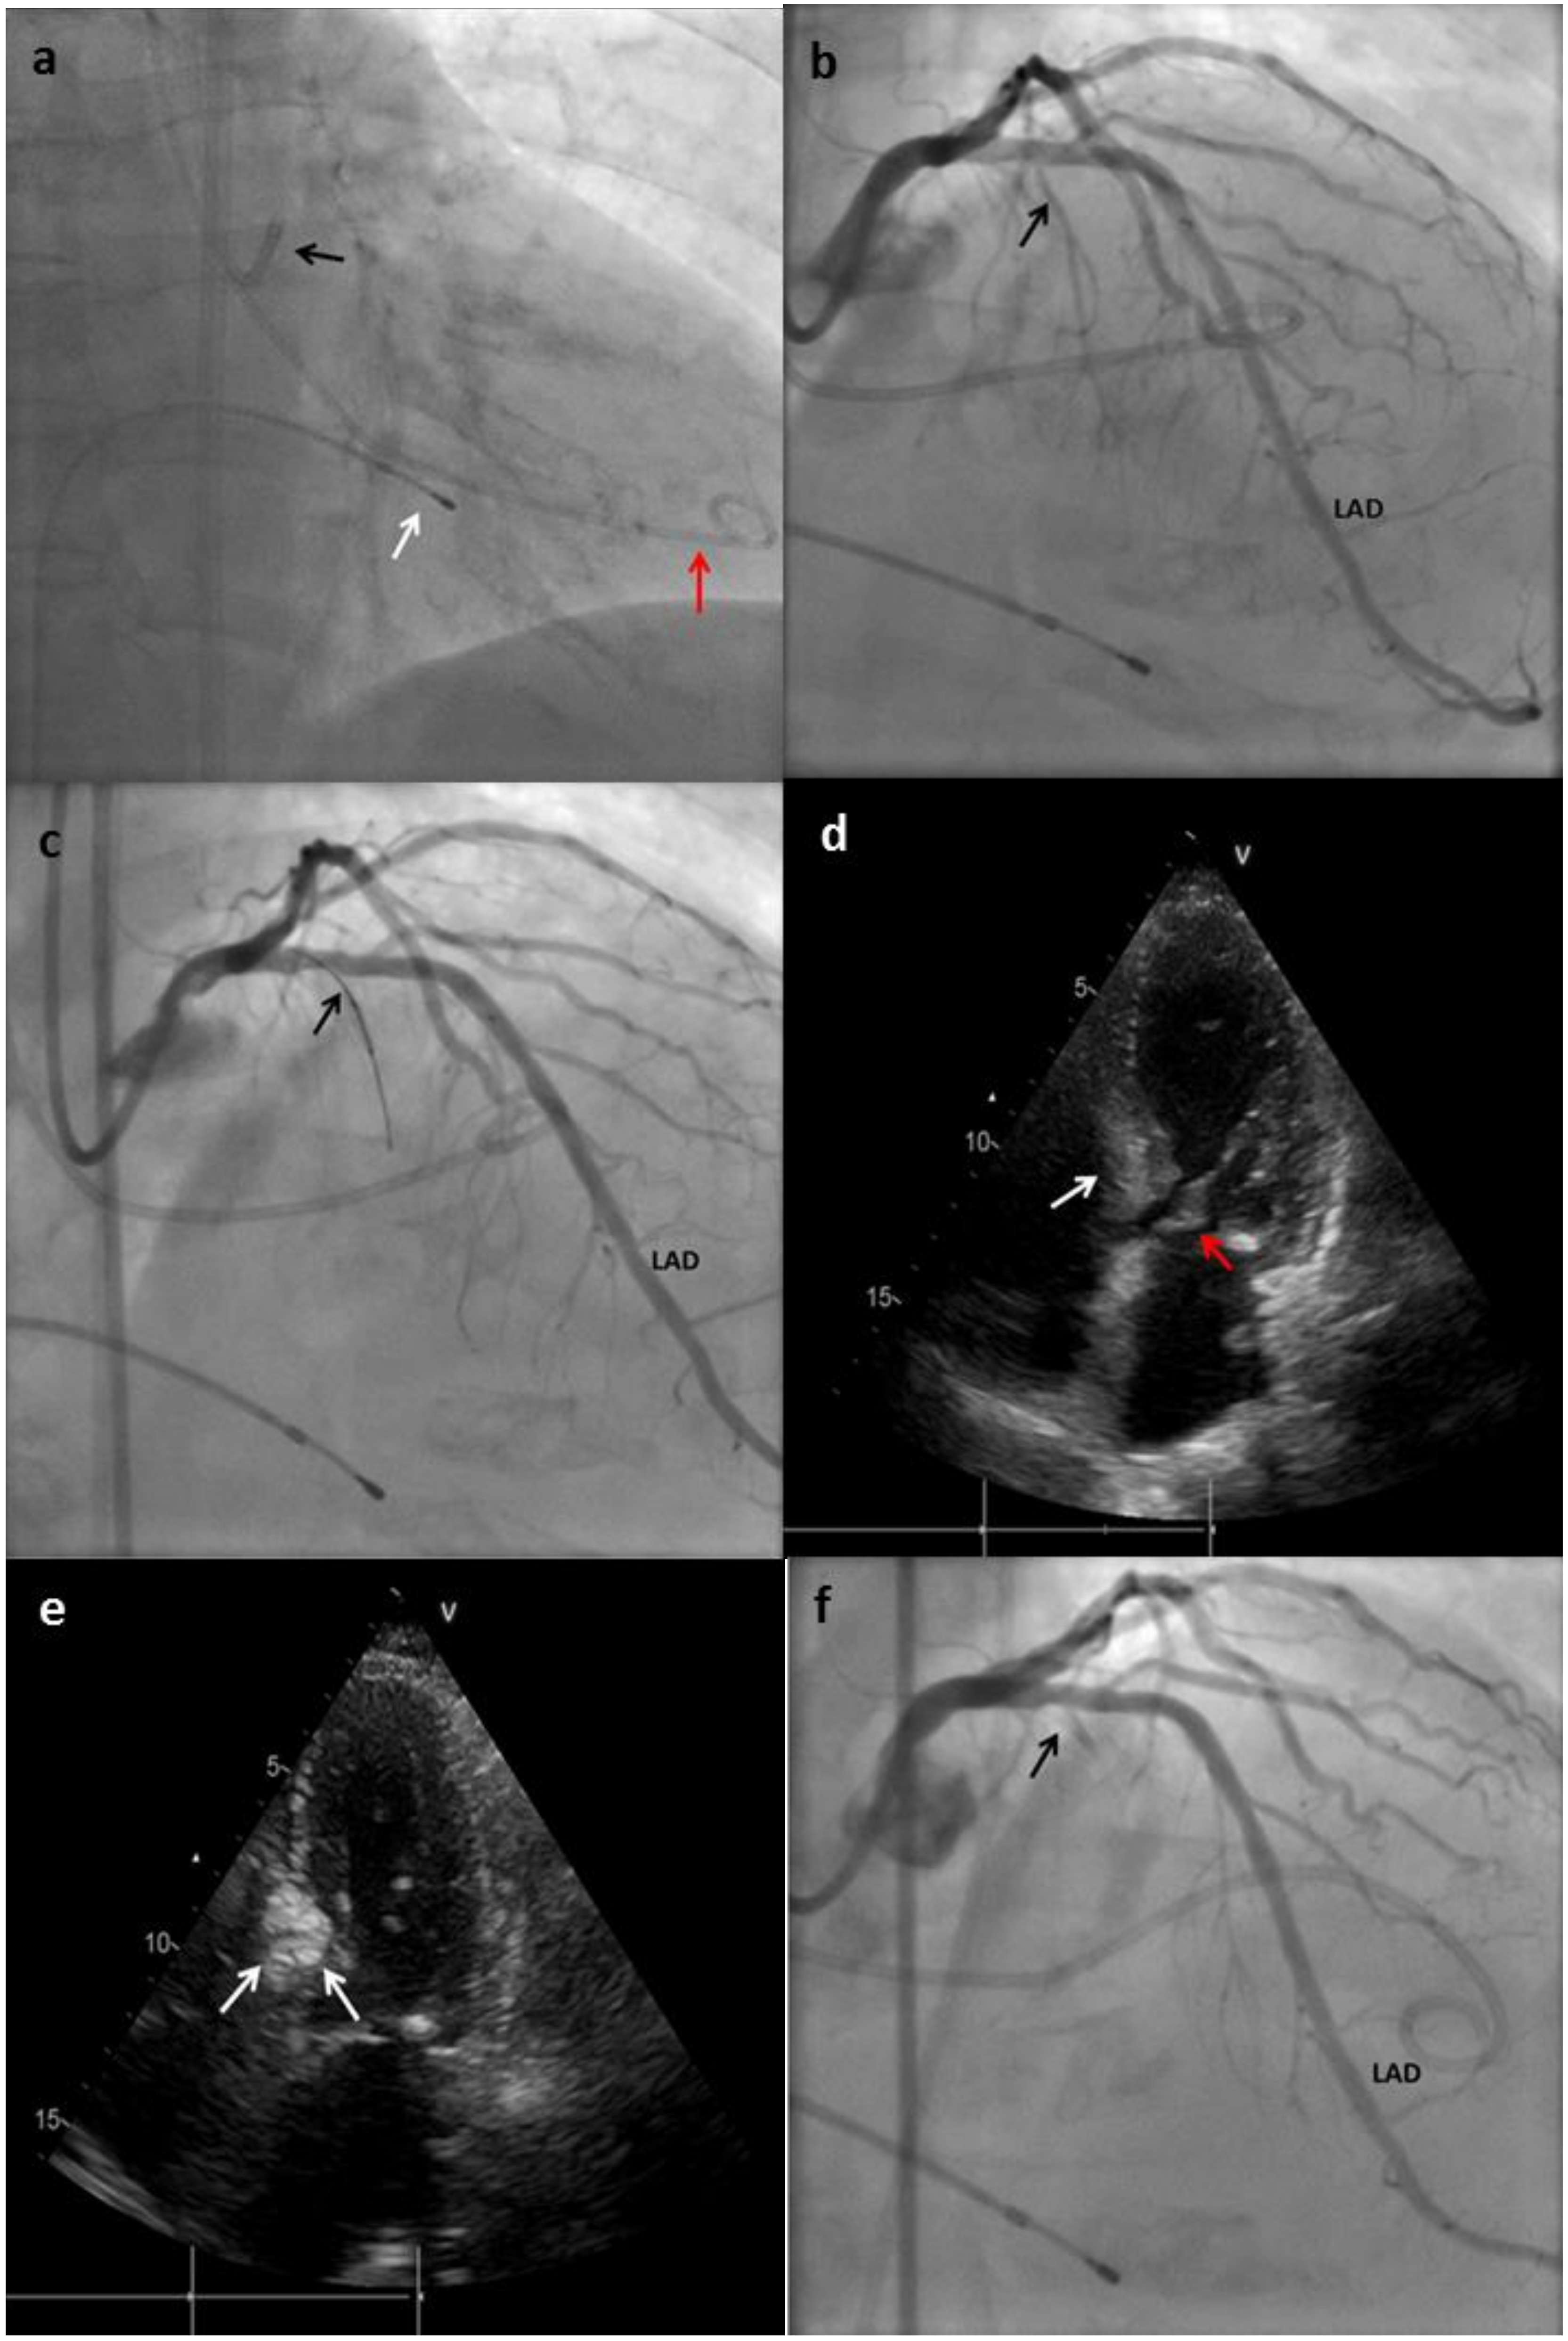

Figure 2.

Main steps of the ASA technique performed in a patient at our center. (a) An extra back-up (EBU) catheter was placed on the ostium of the left main (black arrow); a pig-tail catheter was placed in the left ventricle (LV) for gradient monitoring (red arrow); temporary pacemaker (PM) electro-catheter was placed on the right ventricle (RV) (white arrow). (b) Coronary angiogram showing absence of atheroscletic lesions and the origin of the first septal branch (black arrow). LAD: left anterior descending. (c) The first septal branch is wired and an over-the-wire (OTW) balloon is advanced to this artery (black arrow). (d) Transthoracic echocardiography (TTE) showing hypertrophy of the basal septum (white arrow), which makes contact during systole with the anterior leaflet of mitral valve (red arrow). (e) TTE performed after Gelafundin® (B. Braun, Melsungen, Germany) injection in the septal branch; enhancement of the basal septum can be seen (white arrows), this indicates that the first septal is suitable for ablation. (f) Coronary angiogram showing final result with occlusion of the first septal branch after alcohol injection.